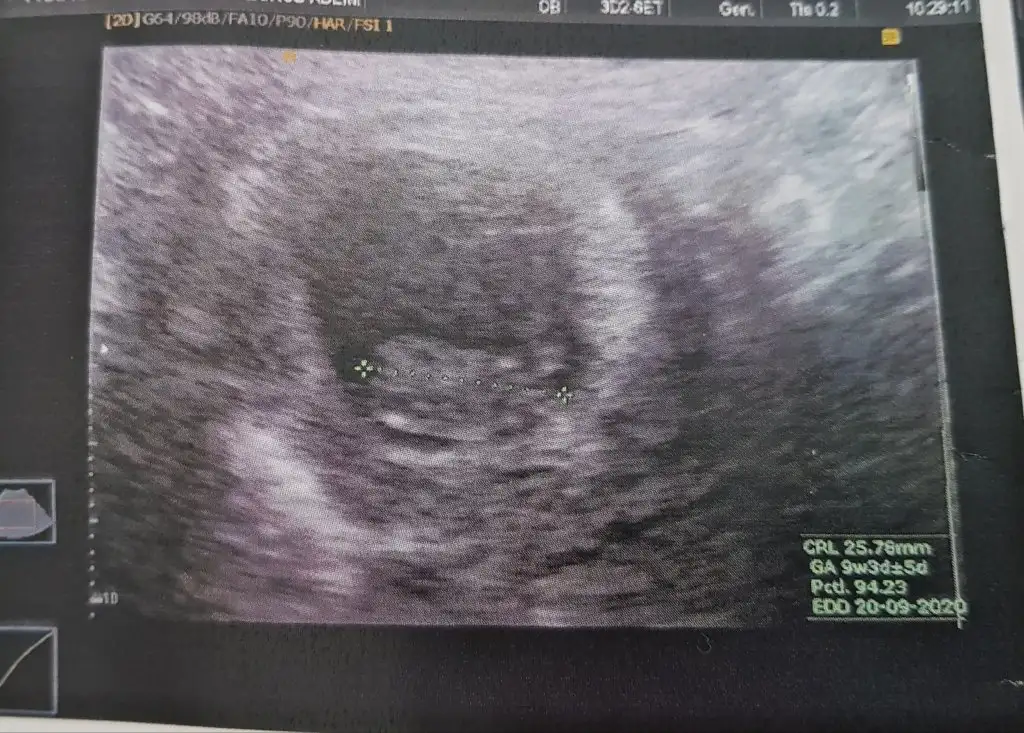

Benim elimde hem kız hem erkek bebeğimin aynı haftalarda usg si var. Şuanki usg, erkek olanınkine daha çok benziyor. Erkek bebeğimi 20.hafta da kaybettiğim için gönlümdeki malum :)) o yüzden çok merak ediyorum. Dediğiniz gibi kısmet bakalım. Önce hayırlı sağlıklı olsunlar inş:)

Bu arada erkek olanınkine benziyor dediğim buranın teorisine göre kız yani kaybettiğim erkek bebeğiminde sağda idi.